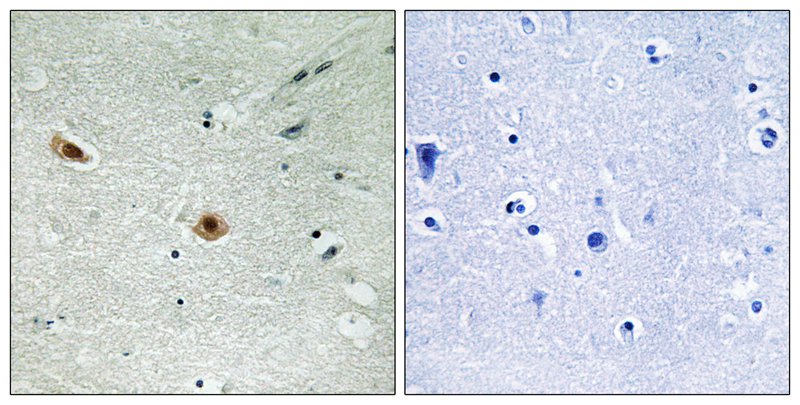

分类: 科研抗体货号: P40424别名: P105-RB; PP105; PP110; RB1;应用: WB,IHC,IF反应种属: Human,Mouse,Rat